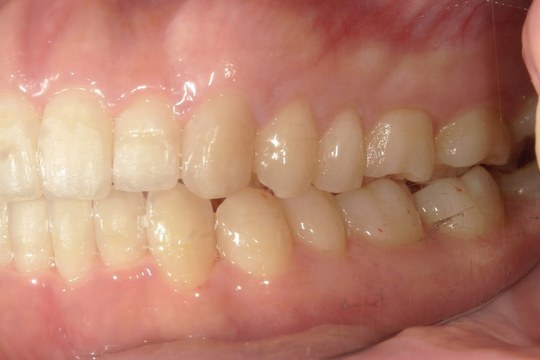

Before

浜松市中央区・自動車学校前駅のインビザラインの症例

M.I. 40代女性

上下の前歯をキレイに並べたい、中心がズレている、という主訴でご来院。上下前歯の叢生を治し、正中を合わせました。

治療の期間:R3. 4/13〜R5. 8/30

治療の価格:88万円